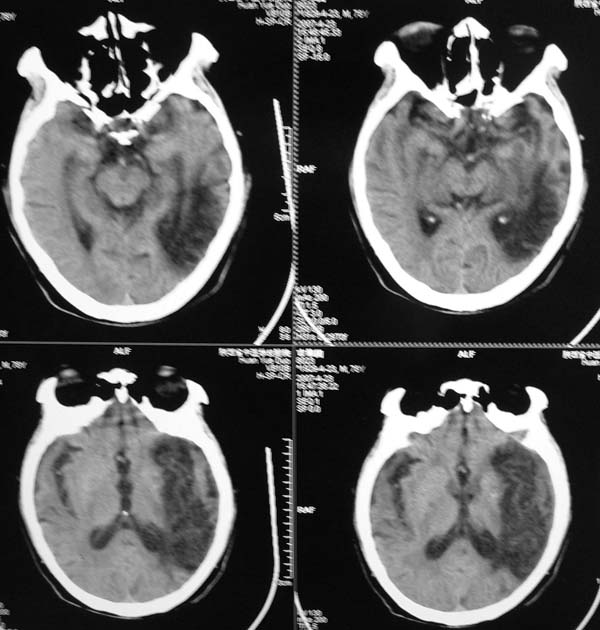

以下是引用star--868在2007-6-15 20:54:00的发言:[br]1.左侧额颞顶部亚急性硬膜下血肿并继续出血 双侧额颞顶部硬膜下积液;[br]2.左颞枕叶、左基底节区脑软化-左侧大脑中动脉栓塞;[br]双侧额颞顶部硬膜下积液应和治疗期间应用高渗脱水剂相鉴别:停用甘露醇后硬膜下积液会逐渐吸收减少,而单纯硬膜下积液无此改变和/或逐渐增多。

以下是引用狙击手在2007-6-15 21:15:00的发言:[br]软化灶就不必说了,主要是混和性血肿的渐变过程。

以下是引用老爱克斯新网客在2007-6-15 20:40:00的发言:[br]1左侧颞叶软化灶,2双侧硬膜下水瘤,3左册硬膜下血肿(多次少量出血),

以下是引用还珠格格在2007-6-16 7:07:00的发言:[br]支持.左侧额颞顶部亚急性硬膜下血肿并继续出血 双侧额颞顶部硬膜下积液;[br]2.左颞枕叶、左基底节区脑软化-左侧大脑中动脉栓塞;